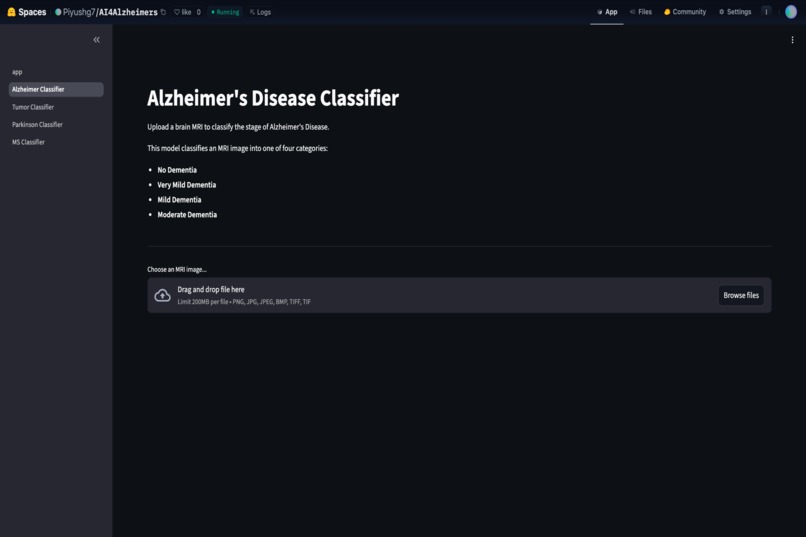

Website Dashboard

MRI upload page